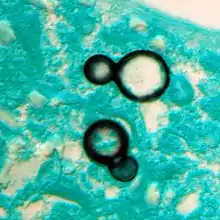

Blastomycosis is caused by dimorphic fungi in the genus Blastomyces, in the phylum Ascomycota and family Ajellomycetaceae. In eastern North America, the most common cause of blastomycosis is Blastomyces dermatitidis, but Blastomyces gilchristii has been associated with some outbreaks. In western North America, many cases of blastomycosis are caused by Blastomyces helicus, which most commonly attacks immunodeficient people and domestic animals. The species Blastomyces percursus causes many cases of blastomycosis in Africa and the Middle East.[14] In Africa, blastomycosis may also be caused by Blastomyces emzantsi, which is often associated with infections outside the lungs.[22]

In endemic areas, Blastomyces dermatitidis lives in soil and rotten wood near lakes and rivers. Although it has never been directly observed growing in nature, it is thought to grow there as a cottony white mold, similar to the growth seen in artificial culture at 25 °C. The moist, acidic soil in the surrounding woodland harbors the fungus.

Inhaled conidia of Blastomyces are phagocytosed by neutrophils and macrophages in alveoli. Some of these escape phagocytosis and transform into yeast phase rapidly. Having thick walls, these are resistant to phagocytosis. Once they have transitioned to the yeast phase, the Blastomyces cells express the protein BAD-1, which helps the yeast cells attach to host cells, and also impairs activation of immune cells while inhibiting release of tumor necrosis factor. [23] In lung tissue, the cells multiply and may also disseminate through blood and lymphatics to other organs, including the skin, bone, genitourinary tract, and brain. The incubation period for pulmonary blastomycosis is 3 to 15 weeks, although 3050% of infections are asymptomatic.[24]